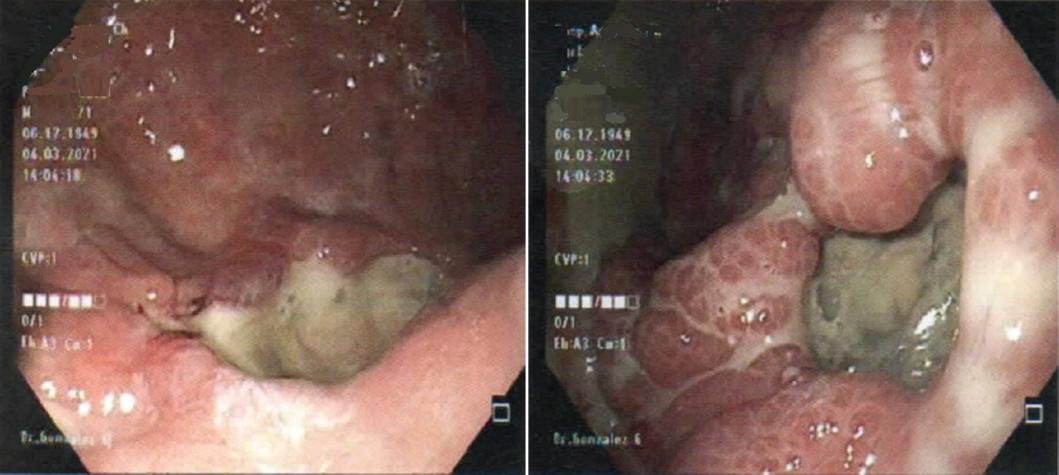

Dentro de los estudios de gabinete, la radiografía de tórax mostró neumopericardio (Fig. 1) y la tomografía computarizada (TC) toracoabdominal una comunicación fistulosa en la curvatura menor al pericardio con presencia de neumopericadio, sin aire libre abdominal (Fig. 2). Decidimos realizar una endoscopia gastroduodenal, con hallazgo de una úlcera gástrica en el cuerpo anterior gástrico y penetración al mediastino, con visualización del movimiento cardiaco a través del pericardio, sin evidencia de sangrado activo (Fig. 3). Posteriormente se realizó un ecocardiograma, sin evidencias de compromiso del gasto cardiaco.

Figura 3 Endoscopia gástrica con presencia de una úlcera sobre el cuerpo del estómago, cercana a la curvatura menor, que penetra al mediastino logrando observar el pericardio.